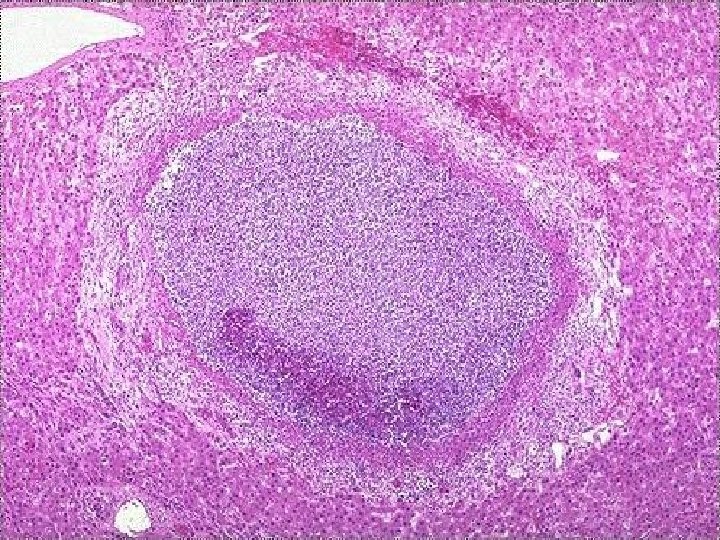

Caseous Necrosis • Gross: Resembles cheese • Micro: Amorphous, granular eosinophilc material surrounded by a rim of inflammatory cells – No visible cell outlines – tissue architecture is obliterated • Usually seen in infections (esp. mycobacterial and fungal infections)

Downloaded from: Student. Consult (on 8 September 2010 02: 58 PM) © 2005 Elsevier

Caseous necrosis -- micro